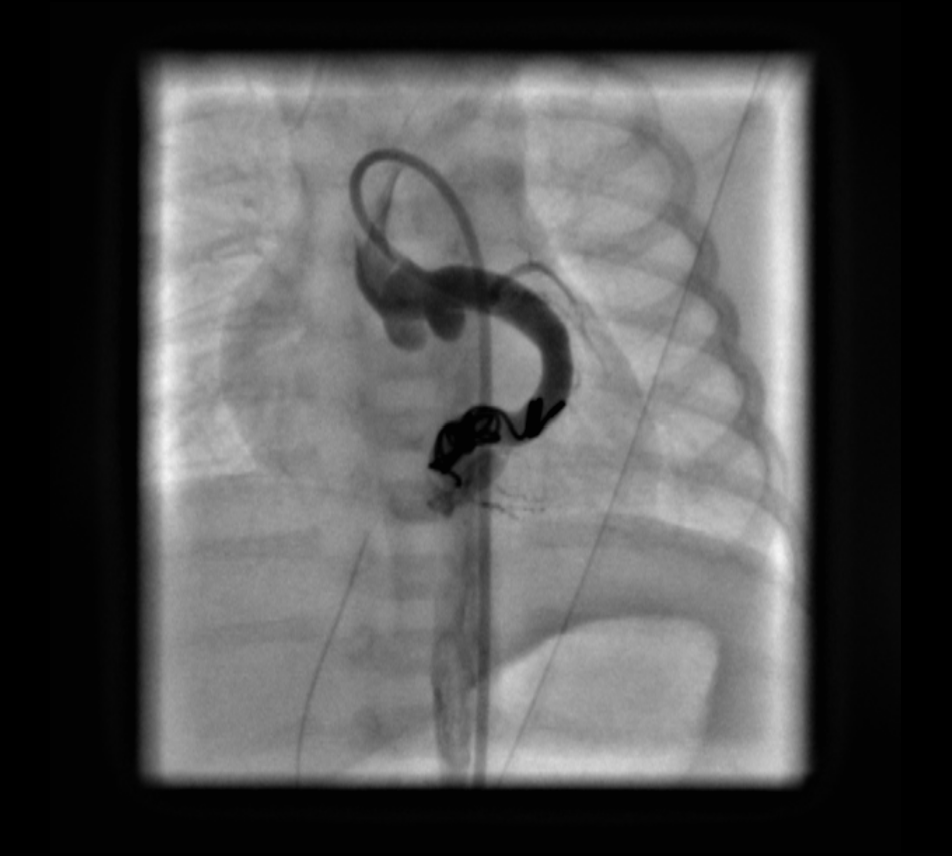

Coronary angiography revealed the fistulous connection to the coronary sinus off of the distal left circumflex coronary artery (LCX). Embolization of the fistula was performed using 2 coils (14 cm × 4 mm distally and 14 cm × 6 mm proximally). Repeated coronary angiography results confirmed the complete occlusion of the fistula and good filling of the left coronary artery (Figures 1-6, fluoroscopic anteroposterior views of the chest).

Figure 3. Fluoroscopic view showing placement of the first embolization coil into the LCX.

Figure 4. Angiogram with contrast after placement of the embolization coil demonstrating a view of the aortic root and LMCA. Mild contrast extension into the coronary sinus is visible.